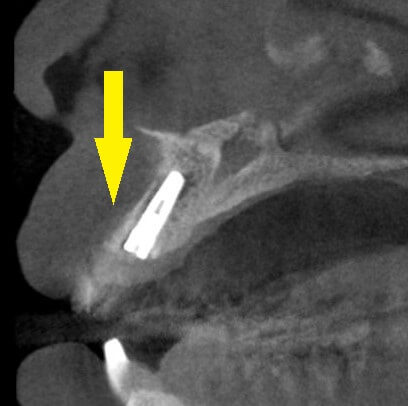

本日、上顎前歯の、抜歯即時インプラント埋入術を行いました。

下の写真下段左が、手術前のCT、下段右が手術後のCTです。